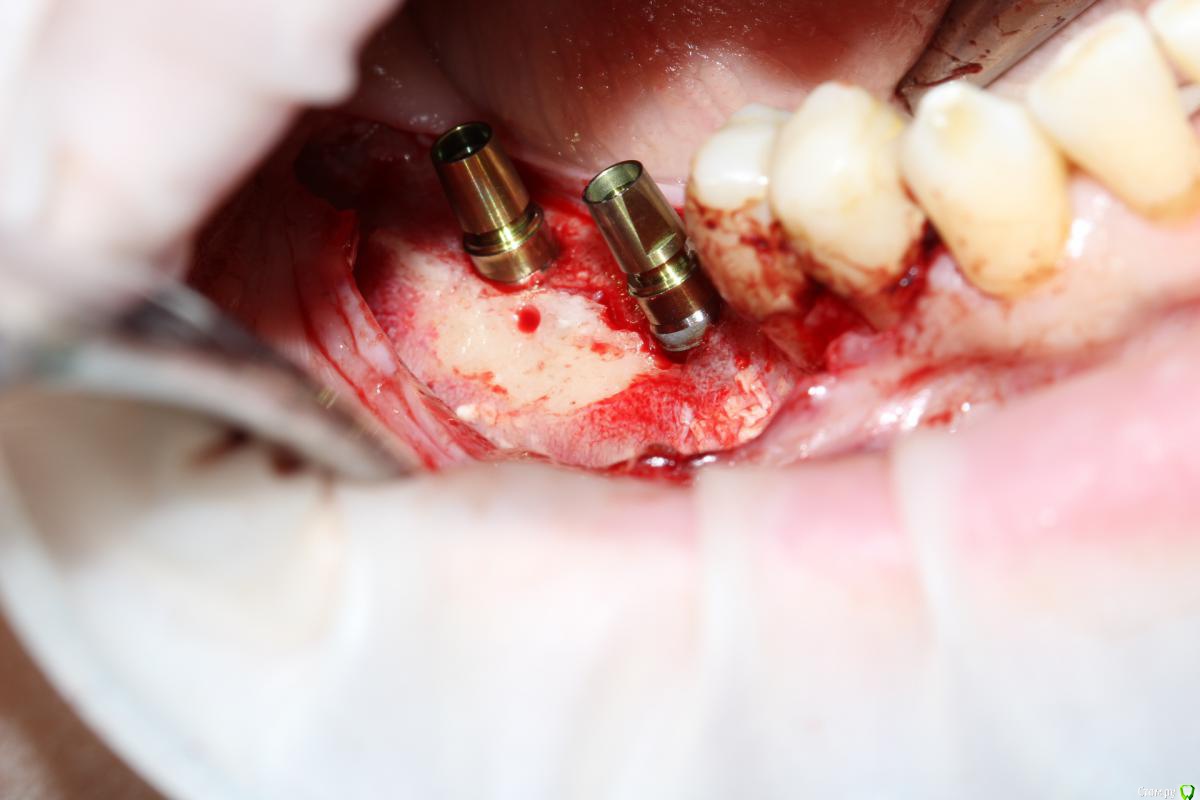

Sahan Опубликовано 22 декабря, 2014 Поделиться Опубликовано 22 декабря, 2014 В четвертом сегменте во время имплантации дополнительно костную пластику проводили? Ссылка на комментарий

Dantist55 Опубликовано 22 декабря, 2014 Автор Поделиться Опубликовано 22 декабря, 2014 В четвертом сегменте во время имплантации дополнительно костную пластику проводили?Да, имплантация с НКР. Ссылка на комментарий